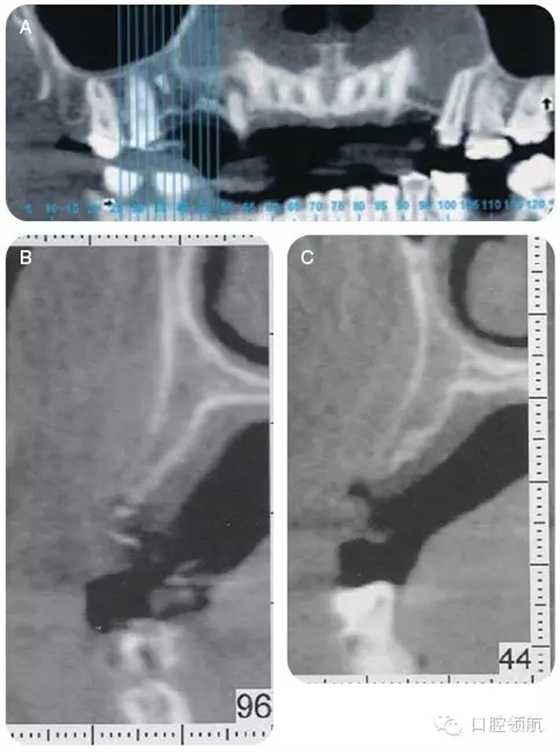

咨詢修復(fù)、牙體牙髓及正畸科,制訂詳細(xì)的治療計(jì)劃。行錐形束CT檢查上頜牙弓,以更好地了解缺損處牙槽嵴的形態(tài)及和上頜竇的鄰接關(guān)系(圖4)。

CT顯示牙槽嵴的垂直距離足夠,為更好地植入種植體,尚需有6~7mm的骨寬度。該區(qū)域的最終治療計(jì)劃包括:引導(dǎo)骨再生,修復(fù)以及咬合重建,包括#4-X-6種植體支持的局部固定義齒。

圖4 (A~C)CT檢查,顯示14號(hào)牙(左上頜第一磨牙)的牙槽嵴水平缺損。

評(píng)估全身系統(tǒng)情況。手術(shù)同意書(shū)重點(diǎn)和患者說(shuō)明了該手術(shù)的優(yōu)點(diǎn)、程序以及可能的風(fēng)險(xiǎn)。通過(guò)和患者更加詳細(xì)的說(shuō)明手術(shù)程序,患者會(huì)感覺(jué)更加放心。CT掃描顯示12號(hào)牙(左上頜第一前磨牙)的水平方向牙槽骨殘余量<3mm。解剖形態(tài)上沒(méi)有明顯障礙。該區(qū)域骨寬度明顯不足,所以采用支帳螺絲以及堅(jiān)固的可吸收膜行GBR。術(shù)前予阿莫西林500mg(手術(shù)開(kāi)始前24小時(shí)開(kāi)始服用,每天3次,持續(xù)10天),布洛芬600mg(根據(jù)需要每4~6小時(shí)1次),vicodin ES(每6小時(shí)1次),以及0.12%氯己定(2次/天)。